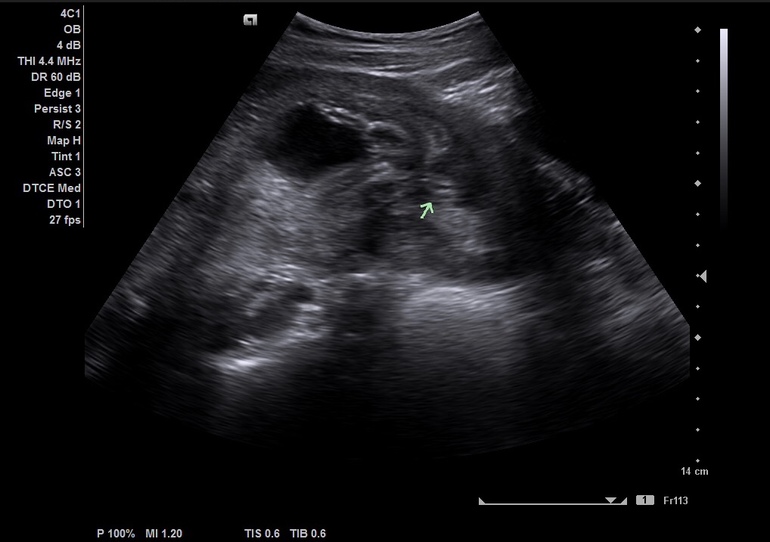

Алиса в Благополучная беременность 7 лет Узи 25,5 недель УЗИ, КТГ, доплер По моему, это точно девочка)))) Посмотрите еще 20 записей на эту тему Отменить Ответить Ольга Да,девочка. 29.10.2018 Ответить ЭлиНа Если смотреть по стрелочки, то это точно девочка )))) 29.10.2018 Ответить Точно девочка?) твп и носик Головка низко!!! Чаты Беременных Выберите чат: Январята-2026 Февралята-2026 Мартята-2026 Апрелята-2026 Майчата-2026 Июнята-2026 Июлята-2026 Августята-2026